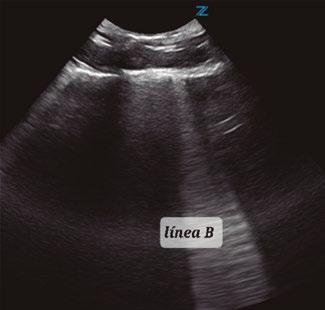

Utilidad clínica de la ecografía pulmonar y cardiaca en urgencias

Similar al signo de desgarro, pero con límites bien definidos que delimitan un nódulo, de origen generalmente inflamatorio o neoplásico (figura 11).

No será necesario rasurar el paciente, salvo perros con una densidad de pelo excesiva (San Bernardo, Chow Chow o Terranova, por ejemplo), y bastará aplicar alcohol para aplastar el pelaje y facilitar el contacto de la sonda.